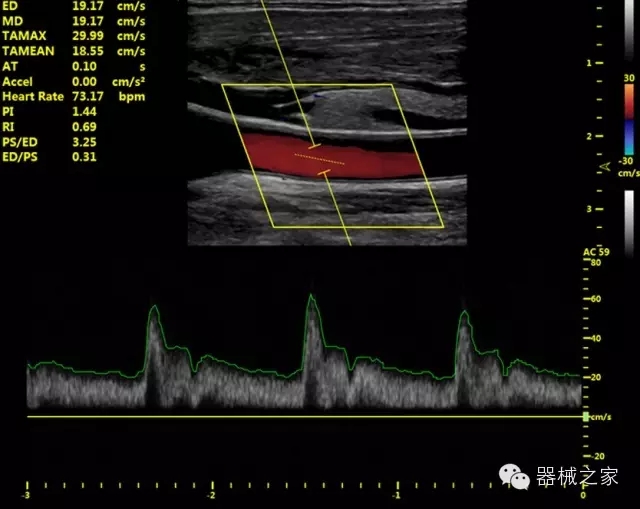

·獨(dú)有的HoloTM PW 實(shí)時(shí)3取樣門(mén)PW成像技術(shù),精確進(jìn)行血管診斷;

·一鍵優(yōu)化B、Color、PW,Auto Doppler自動(dòng)識(shí)別血管位置、偏轉(zhuǎn)角度等,提高工作效率;

·30°超廣角精細(xì)偏轉(zhuǎn)成像技術(shù),更優(yōu)異的頻譜圖像;